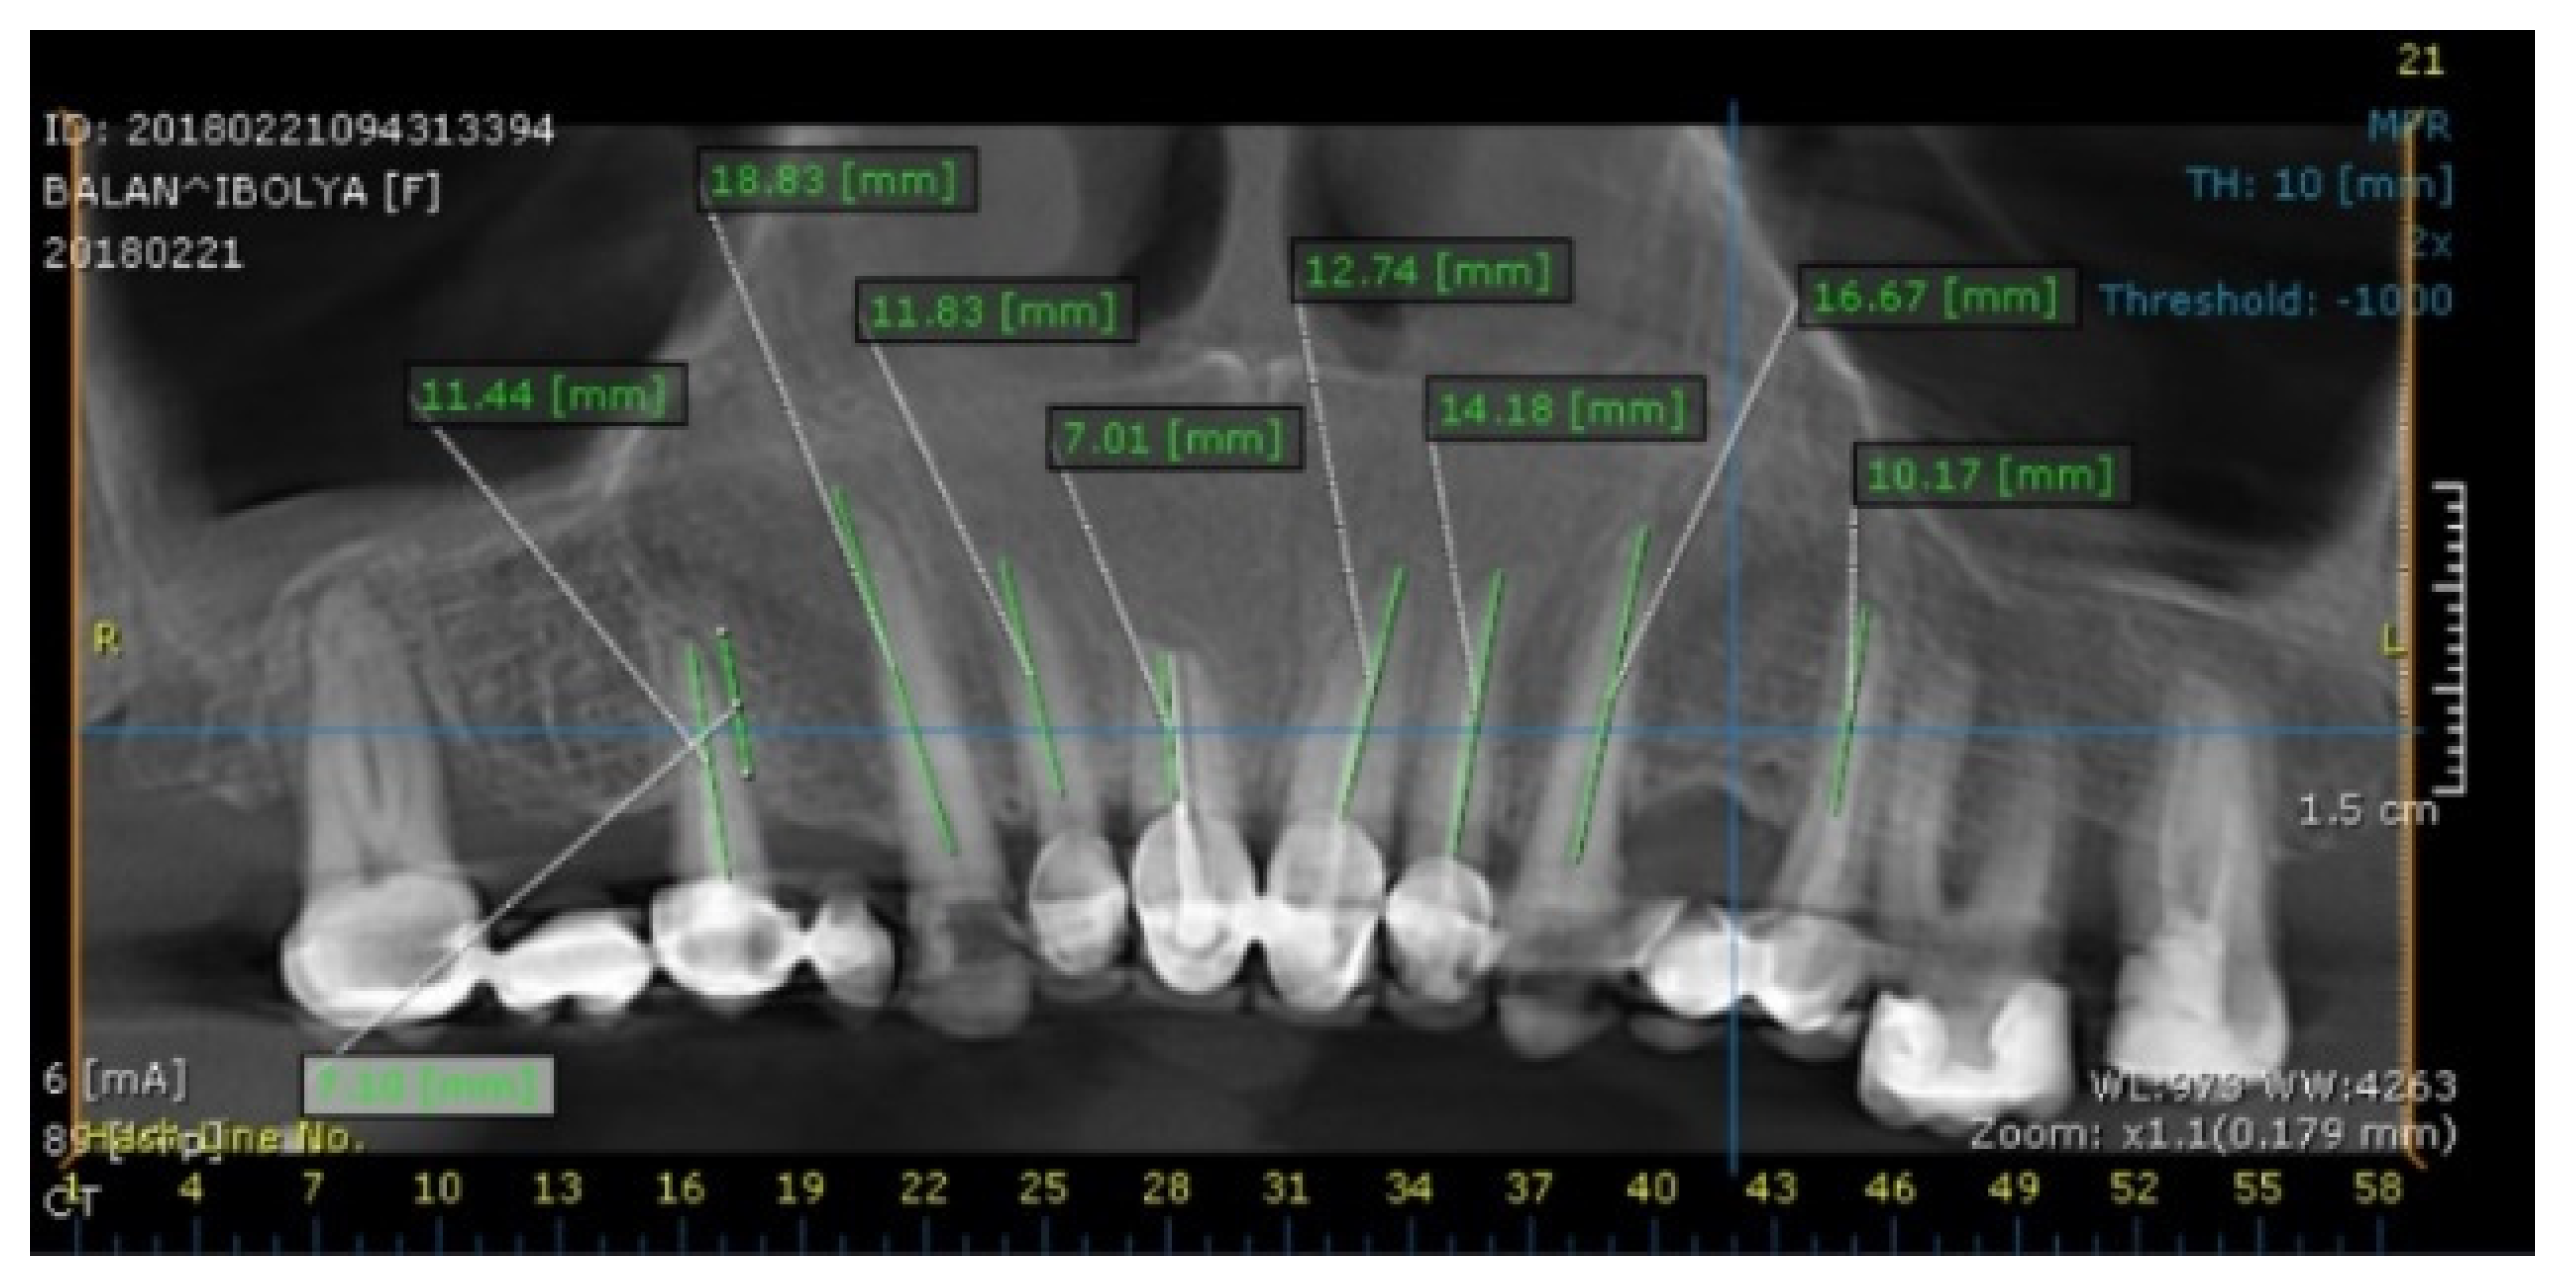

2. Case Report